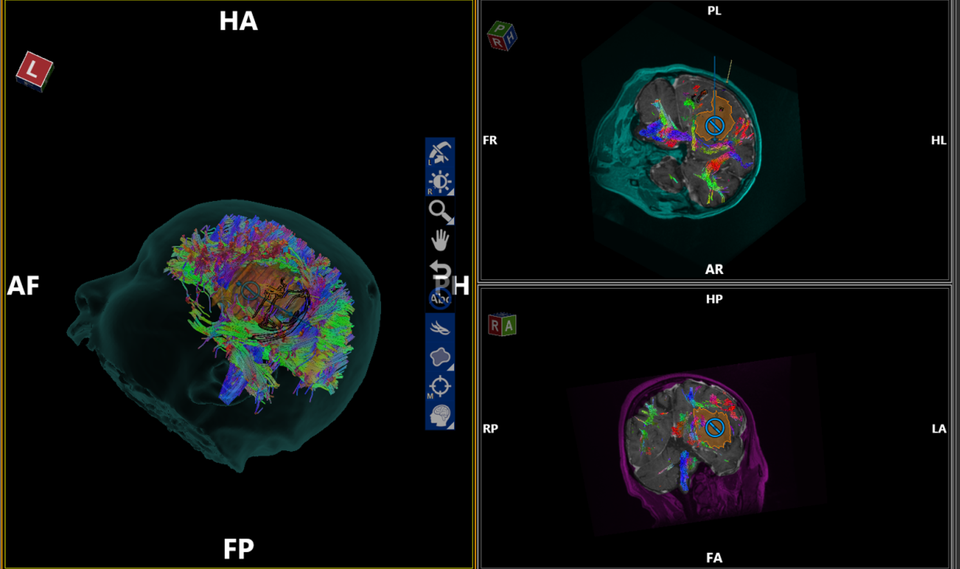

BS Chu Tấn Sĩ cho biết, sau khi gây tê toàn bộ da đầu, bệnh nhân được đặt khung cố định đầu, tiến hành phẫu thuật với hệ thống robot sử dụng công nghệ trí tuệ nhân tạo. Bằng hệ thống định vị hình ảnh 3D chụp cộng hưởng từ khuếch tán, sức căng công nghệ trí tuệ nhân tạo sẽ tự động xử lý để thấy các bó dẫn truyền thần kinh. Nhờ đó, các bác sĩ sẽ tùy chỉnh tối ưu để tiếp cận tổn thương trong phẫu thuật. Bên cạnh đó, hệ thống lập trình phẫu thuật được tích hợp vào phần định vị cho phép phẫu thuật viên lập kế hoạch tối ưu nhất khi phân tích các bó sợi thần kinh quanh tổn thương.

Dưới sự “chỉ đường” của công nghệ trí tuệ nhân tạo và cánh tay robot có kính vi phẫu kỹ thuật số độ phóng đại lớn, độ nét cao, phẫu trường rộng… ê kíp phẫu thuật đã tránh được nguy cơ gây tổn thương các búi dẫn truyền thần kinh mà mắt thường không thể nhìn thấy. Trong suốt cuộc mổ, người bệnh vẫn tỉnh táo, uống nước và trò chuyện với bác sĩ.

BS Tấn Sĩ cho biết, trí tuệ nhân tạo đang tạo ra bước đột phá trong y khoa, cho phép phẫu thuật viên nhìn thấy tương quan giữa tổn thương và các bó dẫn truyền thần kinh, từ đó kế hoạch mổ được lập triển khai tối ưu nhất, tránh làm tổn thương các búi dẫn truyền thần kinh quanh vị trí tổn thương. Ưu điểm vượt trội khác của công nghệ này còn giúp phẫu thuật viên nhìn thấy các vị trí mà nếu mổ bằng vi phẫu khó có thể thực hiện được. Nhờ bệnh nhân tỉnh táo, trong cuộc mổ, bác sĩ vẫn có thể tương tác với người bệnh để đánh giá tính an toàn ngay trong cuộc phẫu thuật.